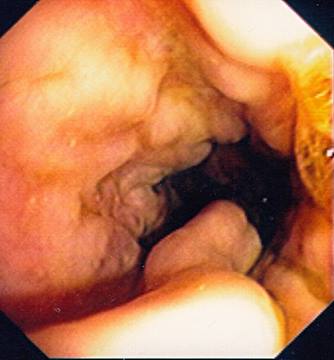

Oesophageal Varices in Banti´s syndrome

Oesophageal Varices in Banti´s syndrome.